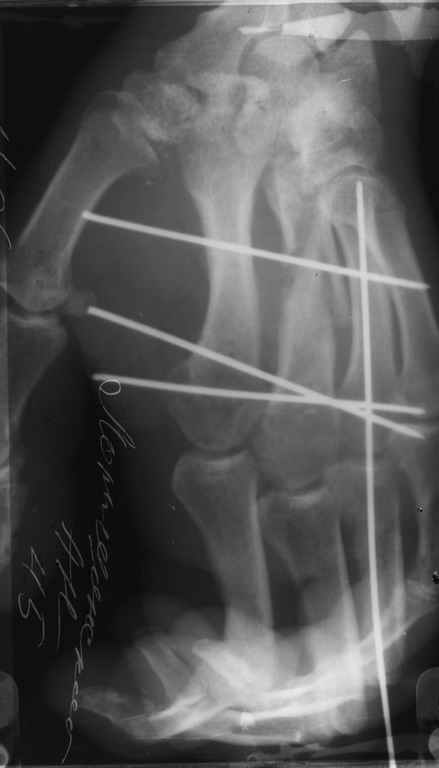

Диагноз: Стойкая Смешанная дермотеногенная контрактура 3,4 пальца правой кисти.